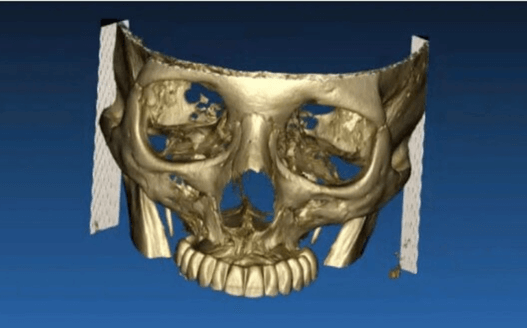

Paciente con edentulismo completo y reabsorción avanzada en maxilar superior.

Rechaza opción removible.

Se planifica rehabilitación completa con 4 implantes Zygoma.

Planificación 3D y confección de férulas quirúrgicas para abordaje guiado.